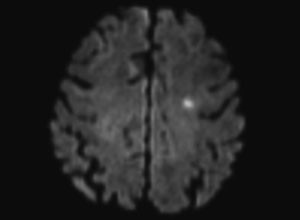

I en ny studie har vi undersøkt 91 pasienter, hvorav 61 ble behandlet med carotisendarterektomi og 30 med carotisangioplastikk og stenting (1). Transkranial doppler med embolideteksjon og for første gang også embolidifferensiering ble utført kontinuerlig under alle prosedyrene. Mikroembolifunn ble relatert til nye kliniske cerebrovaskulære hendelser under prosedyren og nye iskemiske lesjoner på cerebral diffusjonsvektet MR etter prosedyren.

Studien viste at cerebrale mikroembolier, både solide og gassembolier, var assosiert med nye iskemiske hendelser under prosedyren og med nye iskemiske lesjoner på cerebral diffusjonsvektet MR. Flest mikroembolier ble påvist ved behandling av lavekkogene lipidholdige plakk, hvilket samsvarer med tidligere studier som har vist at disse plakkene er mer ustabile enn de mer ekkorike fibrotiske plakkene. Iskemi på cerebral diffusjonsvektet MR før prosedyren var også assosiert med økt frekvens av mikroembolier under prosedyren.

Cerebrale mikroembolier under carotiskirurgi og stenting er altså assosiert med iskemisk hjerneskade undersøkt ved cerebral diffusjonsvektet MR og klinisk vurdering. Cerebrale mikroembolier er et mål på plakkenes instabilitet og risiko for cerebrovaskulære hendelser.